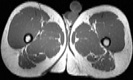

Visible Human male: Sectio transversalis 1987

CT

NMR

Pd                          / T2 \                         T1